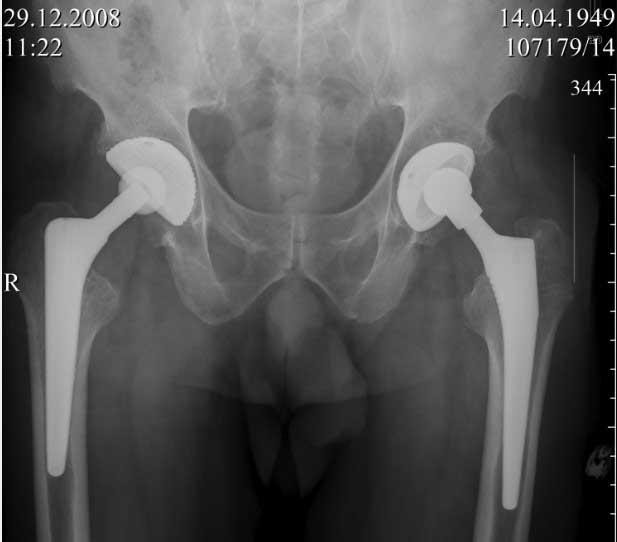

ниже снимок в 2008 году

Пациент 60 лет, мужчина. Оперирован в 2007 году, поочередно оперированы два тазобедренных сустава с интервалом в 4 месяца. В 2008 году оперирован на сердце(аорто-коронарное шунтирование).Операция осложнилась инфицированием операционной раны в области грудины, лечился в гнойном отделении.

В конце 2008 года отметил боли в правой паховой области при опоре на правую ногу. На рентген снимках таза с тазобедренными суставами явных признаков нестабильности вертлужного компонента не обнаружено. В 2009 году нейрохирурги его "успешно" прооперировали на L\3-\4 связывая болевой синдром в правой паховой области с наличием грыжи указанного межпозвонкового диска. Состояние только ухудшилось, больной уже не мог долго сидеть, боль прогрессировала . Его в 2009 и 2010 годах смотрел ортопед, делались рентгенснимки, но почему то приходили к выводу что эндопротез справа стабилен. В марте 2011 года я впервые увидел его, через одну неделю после этого был прооперирован. На операции вертлужный компонент при упоре на него инструментом прокручивался во впадине и без труда был извлечен.